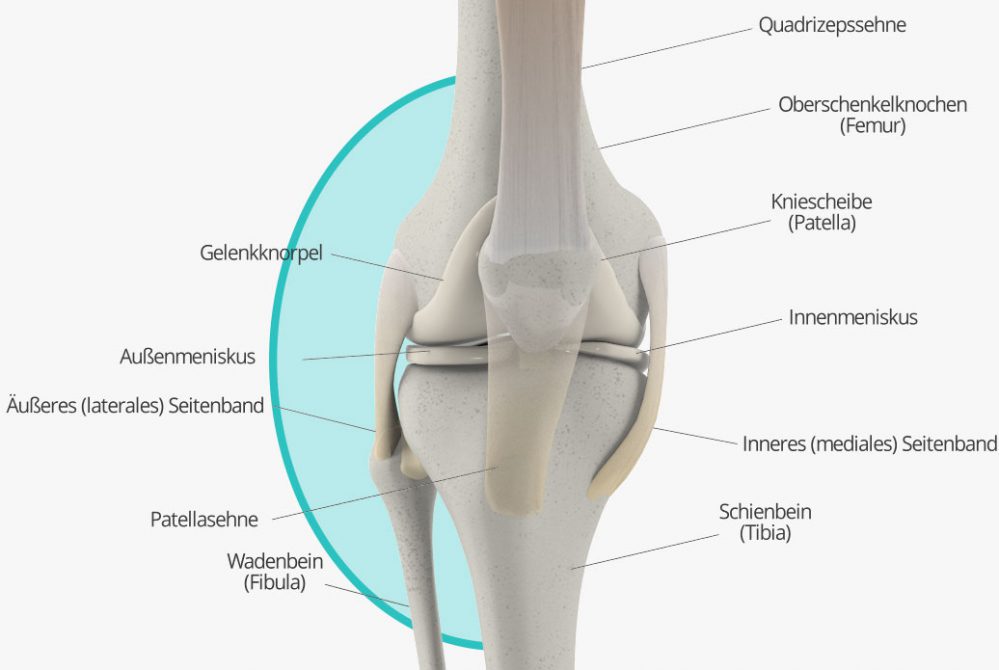

Aus dem Auftreten des Knieschmerzes an der Innenseite des Knies kann man noch keine eindeutige Diagnose ableiten: Zwar ist er oft ein Zeichen dafür, dass der Innenmeniskus geschädigt ist; doch auch andere Ursachen kommen infrage, beispielsweise eine Schleimbeutelentzündung, eine Sehnenreizung oder ein Sehnenschaden an der rückseitigen Oberschenkelmuskulatur (sog. Kniebeuger). Auch allgemeiner Gelenkverschleiß kann unter gewissen Umständen Schmerzen an der Knieinnenseite verursachen. Auch hier ist also eine genaue Untersuchung durch den Facharzt unabdinglich, um eine eindeutige Diagnose zu stellen.

Natürlich können Knieschmerzen auch an der Knieaußenseite vorkommen. Nicht selten deuten Schmerzen in diesem Bereich auf einen Schaden an Meniskus oder Außenband hin. Es gibt aber noch viele weitere Krankheitsbilder, die Schmerzen an der Außenseite des Kniegelenks verursachen können. Oftmals handelt es sich zunächst „nur“ um die Folgen einer einseitigen Belastung des Knies, zu der es beispielsweise durch Hüft-, Fuß- oder Kniefehlstellungen kommen kann. Werden diese Ursachen rechtzeitig behandelt (beispielweise mit Physiotherapie), legt sich auch der Schmerz meist schnell wieder. Bleibt die einseitige Belastung jedoch längerfristig unbehandelt, können dauerhafte Schäden am Kniegelenk (z.B. Knorpelschäden, Arthrose) die Folge sein. Auch das so genannte Läuferknie, ein Sonderfall der Überbeanspruchung des Kniegelenks, sowie Schäden an den Sehnen können Knieschmerzen an der Außenseite des Gelenks verursachen.

Knieschmerzen, die an der Vorderseite des Knies auftreten, stehen zumeist mit der Patella, (Kniescheibe) in Zusammenhang. Schäden an und Probleme mit der Kniescheibe können diverse Ursachen haben. Wie so oft, kann der Schmerz vielfach auf Überbeanspruchung oder Fehlbelastung – oder Verschleißerscheinungen in deren Folge – zurückgeführt werden. Doch auch Krankheitsbilder wie das Plicasyndrom oder eine so genannte Patellaluxation können Ursachen für Beschwerden vorn am Knie sein.

Schmerzen am Knie, die in der Kniekehle lokalisiert sind, kommen ebenfalls häufig vor. Sie sind oft durch eine Bakerzyste bedingt, eine Auswölbung der Gelenkkapsel, die durch chronische Reizung verursacht wird. Doch auch eine Arthrose, Meniskusschäden oder Probleme mit den Blutgefäßen können Ursache von Schmerzen in der Kniekehle sein.

Manchmal lässt sich der gefühlte Schmerz auch direkt der Kniescheibe zuordnen, zum Beispiel, weil der Schmerz direkt in Zusammenhang mit einer Bewegung der Kniescheibe steht. Im Prinzip kommen hier als Ursache all die Krankheitsbilder in Frage, die auch allgemein bei Schmerzen vorne im Knie mögliche Diagnosen darstellen. Dazu zählen insbesondere das Plicasyndrom, die Patellaluxation sowie Fehl- und Überbelastung und Verschleiß bis hin zur Arthrose. Doch auch etwa ein Bruch der Kniescheibe kommt als Ursache in Frage. Ein Orthopäde kann auch hier die Ursache leicht über eine Anamnese, körperliche Untersuchung sowie in der Regel auch bildgebende Verfahren feststellen.